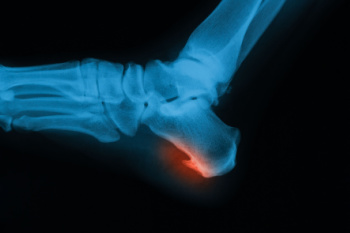

Types of Bone Spurs in the Feet

Bone spurs in the feet, also called osteophytes, form when the body produces extra calcium in response to stress, friction, or inflammation. These growths are not always painful, but they can interfere with nearby tissues and cause discomfort. Heel spurs are one of the most common types. They develop beneath the heel bone from strain on the plantar fascia or at the back of the heel due to tension from the Achilles tendon. Tarsal spurs occur in the midfoot, either on the top or bottom, and often make wearing shoes painful because of pressure against the spur. Toe joint spurs typically affect the big toe, leading to stiffness, limited motion, and pain while walking, especially when arthritis is present. A podiatrist can determine the cause of the bone spur, relieve pressure on surrounding structures, and recommend treatment. If you are experiencing foot or heel pain, it is suggested that you schedule an appointment with a podiatrist for an exam and appropriate treatment.